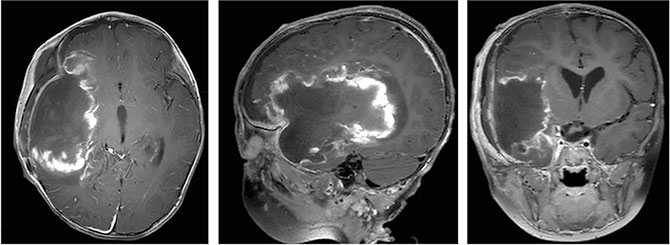

在团队的通力合作下,肿瘤最终被完整切除,切除组织大小约13×7×4厘米。术后患儿恢复良好,意识状态逐渐改善,可自主进食,右侧肢体肌力逐步恢复,术后一周已能在搀扶下站立,未出现新发神经功能障碍。复查头部MR显示肿瘤全切,周围脑组织受压解除,脑中线结构复位。在近期的一次复查中,小初已经可以像正常孩子一样跑跑跳跳了。

肿瘤被完整切除,切除组织大小约13×7×4厘米。

术后影像资料显示肿瘤全切。